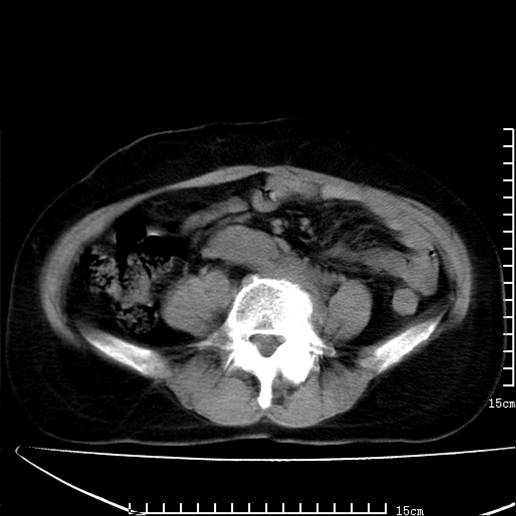

以下是引用pujunzhi在2008-5-30 15:31:00的发言:[br]异位肾—盆腔肾。当看到肾窝无肾脏时,要想到孤立肾和异位肾,异位肾最常见是盆腔肾,偶见胸腔,易误认为肺占位,只要想到就不会漏诊。建议增强扫描。